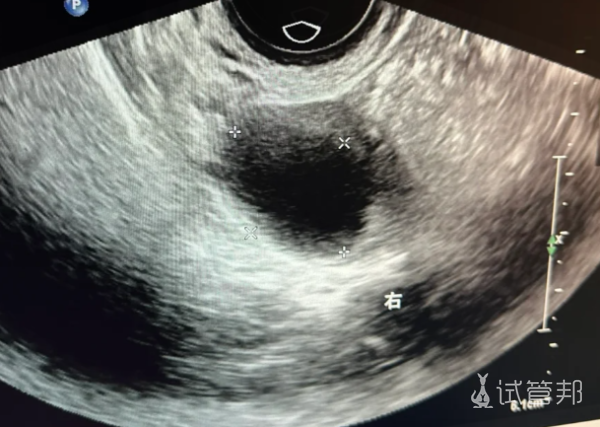

2025-03-27卵子不排,卵泡黄素化了,备孕失败

第一次促排,卵泡成熟后打了破卵针,我还满怀信心地去海边玩了几天,结果卵泡没排,出现卵泡黄素化了。医生让我别灰心,六月继续第二次。这次卵泡和内膜都不错,打了破卵针后我还去爬山了,结果还是没怀。

七月第3次促排,卵泡和内膜依然很好,但打了破卵针又没破。朋友们说促排3次得休息,我和老公商量后决定做个输卵管造影。结果显示两侧都通,医生建议我继续促排。

十月第4次促排,卵泡不长,打了3针尿促才长起来,换了破卵针终于排了,但还是没怀。十一月我放弃了去医院,在家喝中药颗粒监测排卵,依然没怀。

十二月我彻底放松了,月经推迟了10天自己来了。新年前我又去了医院,开始第5次促排。这次卵泡和内膜都很好,打了破卵针也排了,我甚至感觉到了着床,但排卵第11天,试纸显示还是没怀。